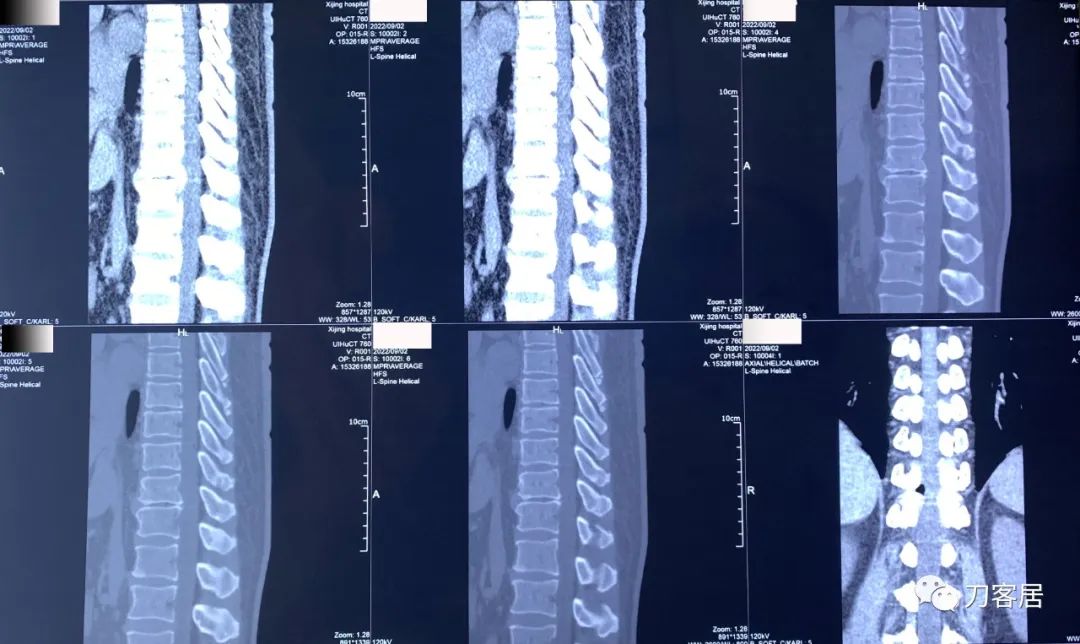

图20. 20220902西京医院胸腰段三维CT扫描重建01,提示胸11-12椎间隙变窄,椎体前后缘骨质增生,有椎管狭窄,但并不那么严重。

图21. 20220902西京医院胸8-腰1三维CT扫描重建02, 胸8-9, 胸9-10,胸10-11,胸11-12,胸12-腰1椎间隙CT扫描,椎管狭窄存在,但并不严重。

图22. 20220902西京医院胸8-腰1三维CT扫描重建报告